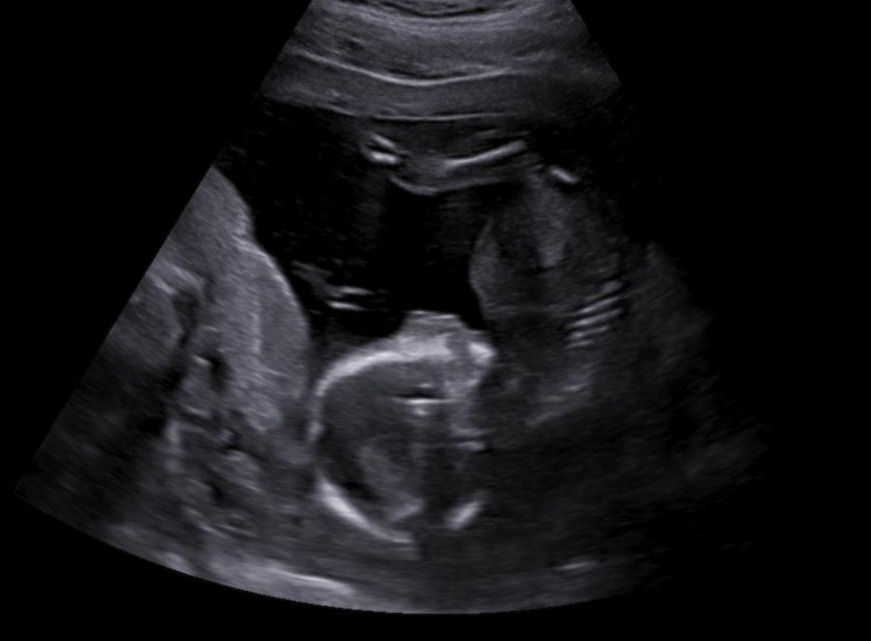

V 17. týdnu jdu na další běžnou kontrolu, asi měsíc po prvotrimestrálním screeningu a trochu doufám, že už by mi mohli odhalit pohlaví děťátka. Určitě si to s manželem chceme nechat říct, abysme už si mohli připravovat výbavičku a všechno v návaznosti na konkrétní pohlaví. Celá rodina netrpělivě očekává výsledek a všichni se mě poté vyptávají, jak to dopadlo. Tentokrát jsem na kontrole měla jen porodní asistentku a ne přímo doktora a ta mi sdělila, že nemá prý ještě tak vytrénované oko, aby to poznala. Takže odcházím opět bez výsledku :D Trošku více bych si přála holčičku, tak mám aspoň o měsíc delší naději, že to může vyjít. Manželovi to je jedno, ten prý nemá preferenci. Za holčičku i kluka bude prý stejně rád. Ideální situace <3

Také dostávám váhový odhad miminka na 190 gramů, což je asi o 50 gramů více, než je horní hodnota váhového odhadu v mé těhotenské aplikaci. No, bude to asi pěkný macík :D Ostatně, břicho už mi také začíná dost slušně růst.

Ve čtvrtém měsíci už se vám výrazně snižuje riziko samovolného potratu, takže pokud jste došly až sem, je to výborná zpráva. Děťátku se začínají tvořit řasy a obočí. Co je dále zajímavé v tomto období, že vaše miminko začíná poprvé rozpoznávat chutě jídel, které pozřete a vytváří si tak apetit do budoucna. Co chutná vám, bude chutnat pravděpodobně i jemu. Na začátku čtvrtého měsíce je miminko velké asi 10cm a váží zhruba 70 gramů a na konci měsíce už je asi 15cm dlouhé a váží zhruba 240gramů. Jeho srdíčko také už přepumpuje zhruba 23 litrů krve za den.